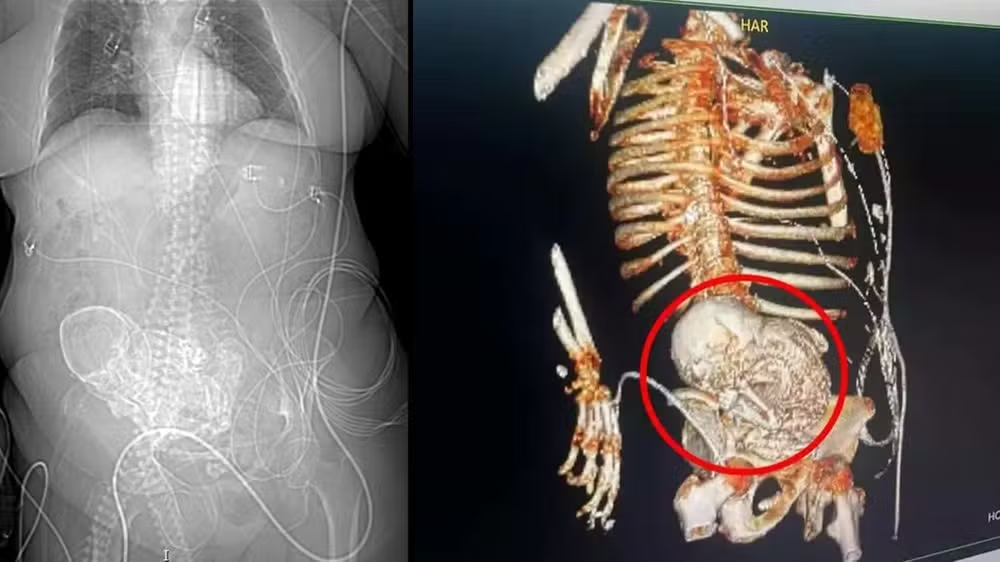

Uma idosa de 81 anos, moradora de Aral Moreira, em Mato Grosso do Sul, foi encaminhada para o Hospital Regional de Ponta Porã, onde descobriu que carregava um “bebê de pedra” no abdômen por cerca de 56 anos, quando teve sua última gestação.

Na última quinta-feira (14), a idosa foi admitida no hospital com uma infecção grave. Uma tomografia revelou a presença do feto calcificado no abdômen. A equipe de obstetrícia realizou uma cirurgia para a retirada, mas a mulher faleceu no dia seguinte devido a uma infecção generalizada decorrente de uma infecção urinária.

“A litopedia é um tipo raro de gravidez ectópica [tipo de gravidez quando o óvulo fertilizado se desenvolve fora do útero], e ocorre quando o feto de uma gravidez abdominal não reconhecida morre e se calcifica. O ‘bebê de pedra’ é resultante e pode não ser detectado por décadas, e pode causar complicações futuras”, comentou o Derzi ao G1.